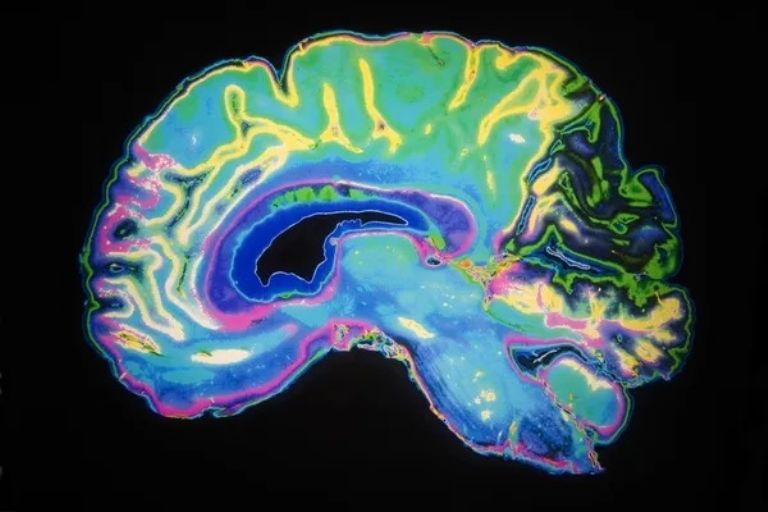

Un equipo de investigadores del CONICET (Argentina) y la Universidad de Harvard dio un paso crucial en la comprensión de la neurogénesis adulta. Publicado en la prestigiosa revista Science Advances, este estudio revela los mecanismos moleculares que participan en la maduración de las neuronas en el hipocampo del cerebro adulto, un descubrimiento que podría revolucionar el tratamiento de enfermedades neurodegenerativas como el Alzheimer, así como condiciones relacionadas con el envejecimiento y las lesiones cerebrales.

La investigadora del CONICET (Consejo Nacional de Investigaciones Científicas y Técnicas), Damiana Giacomini, explica que el equipo logró identificar y mapear los factores de transcripción —genes que regulan la expresión de otros genes— durante el proceso de maduración de una célula madre a una neurona madura en el giro dentado del hipocampo. "Esto aporta un nuevo escenario porque el hipocampo es una de las zonas afectadas por enfermedades neurodegenerativas como el Alzheimer. Entonces, entender qué sucede en situaciones fisiológicas normales permitirá luego, a largo plazo, pensar cómo prevenir o minimizar situaciones patológicas", afirma Giacomini.

El equipo de investigación empleó una innovadora técnica de datación de nacimiento en ratones, combinada con la secuenciación de ARN de núcleo único (sn-RNAseq). Esto les permitió estudiar los genes de casi 40,000 neuronas de distintas edades y definir cuatro estados principales de desarrollo: células madre neurales quiescentes, células proliferativas, células granulares inmaduras postmitóticas y células granulares maduras.

El estudio, dirigido por Alejandro Schinder del CONICET, proporciona un atlas genético sin precedentes que permitirá estudiar la neurogénesis adulta en diversas especies, incluyendo a los humanos. Este avance abre nuevas posibilidades para la reprogramación neuronal, una técnica que busca convertir células en neuronas para reparar funciones alteradas. Giacomini destaca que para reprogramar neuronas efectivamente, es esencial conocer los factores de transcripción que otorgan identidad y características distintivas a cada etapa del desarrollo neuronal.